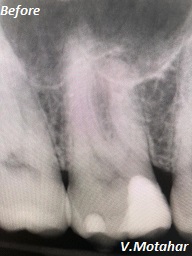

Root Canal treatment on Lower molar tooth immediate after the Root Filling!

before

after

Root canal treatment on three rooted tooth! which had 4 canals!